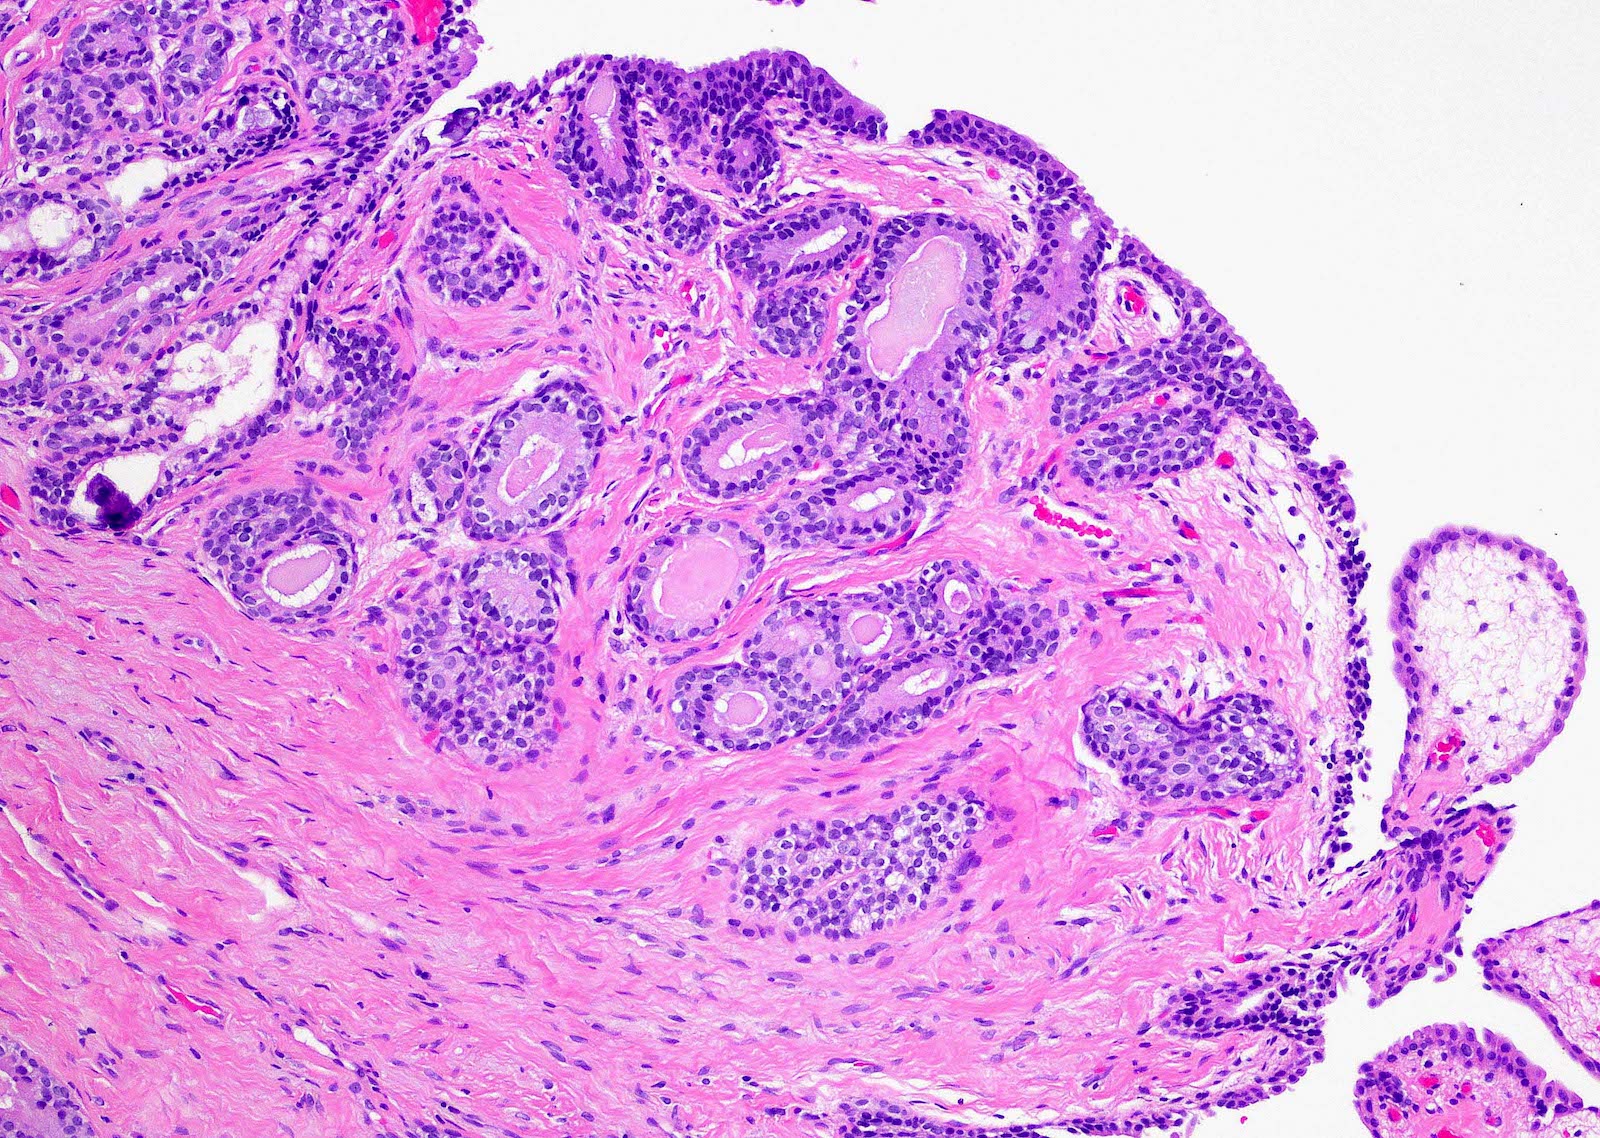

- Fibroepithelial urethral polyp (Am J Surg Pathol 2005;29:460):

- Pattern 1: most common pattern includes the following features

- Broad cloverleaf-like and club-like projections covered by normal urothelium and composed of dense fibrovascular stroma with florid cytitis cystica et glandularis (most common morphologic variant)

- Back to back glands present in the stalk

- Anastomosing nests of benign urothelial cells resembling inverted papilloma

- Dilated cysts with intracystic papillary contents

- Degenerative reactive atypia of stromal cells

Microscopic (histologic) images

Contributed by Y. Albert Yeh, M.D., Ph.D.

Fibroepithelial polyp